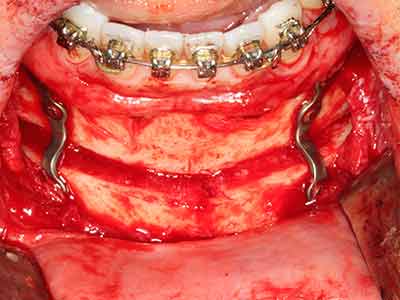

Il tessuto osseo non è semplicemente una struttura minerale, ma contiene anche una percentuale significativa di fibre di collagene. Ciò significa che non possiede solo una buona forza di compressione, ma anche un certo livello di flessibilità che è possibile sfruttare durante l'esecuzione degli accrescimenti di osso. Nella procedura di espansione classica con incisione ossea, la cresta alveolare atrofizzata viene incisa longitudinalmente ed espansa con cautela dopo aver raggiunto una profondità di osteotomia adeguata (figg. 13-16), idealmente senza una sostanziale rimozione del periostio (Brugnami, Caiazzo et al. 2014, Stricker, Fleiner et al. 2014). I sistemi a piastra e vite con distanza di espansione incrementale si sono dimostrati efficaci nella separazione delle due lamelle ossee restando al di sotto della soglia di frattura. In generale, sono richieste larghezze dell'osso residuo di almeno 3-4 mm (Chiapasco, Zaniboni et al. 2006) per garantire un'adeguata flessibilità e una copertura sufficiente dell'osso per gli impianti futuri. Se necessario, un'osteotomia di rilascio verticale su uno o più lati può migliorare la flessibilità. Una combinazione con ulteriori tecniche di accrescimento, in particolare dal lato buccale, è stata descritta come un'alternativa alla tecnica classica.

La procedura di incisione è particolarmente atraumatica e non comporta una perdita significativa di dimensione durante l'utilizzo delle seghe piezoelettriche, così come non si notano differenze rilevanti tra impianti in mandibole incise e impianti in una cresta alveolare senza deficit osseo (Chiapasco, Zaniboni et al. 2006, Danza, Guidi et al. 2009). Una sufficiente irrigazione continua è essenziale, tuttavia, in particolare con incisione profonda e localmente ristretta, per prevenire la sollecitazione termica nelle regioni apicali dell'osteotomia.

Fig. 13: l'irrigazione adeguata con l'osso residuo largo 4 mm è essenziale durante l'incisione ossea di questo paziente di 52 anni.